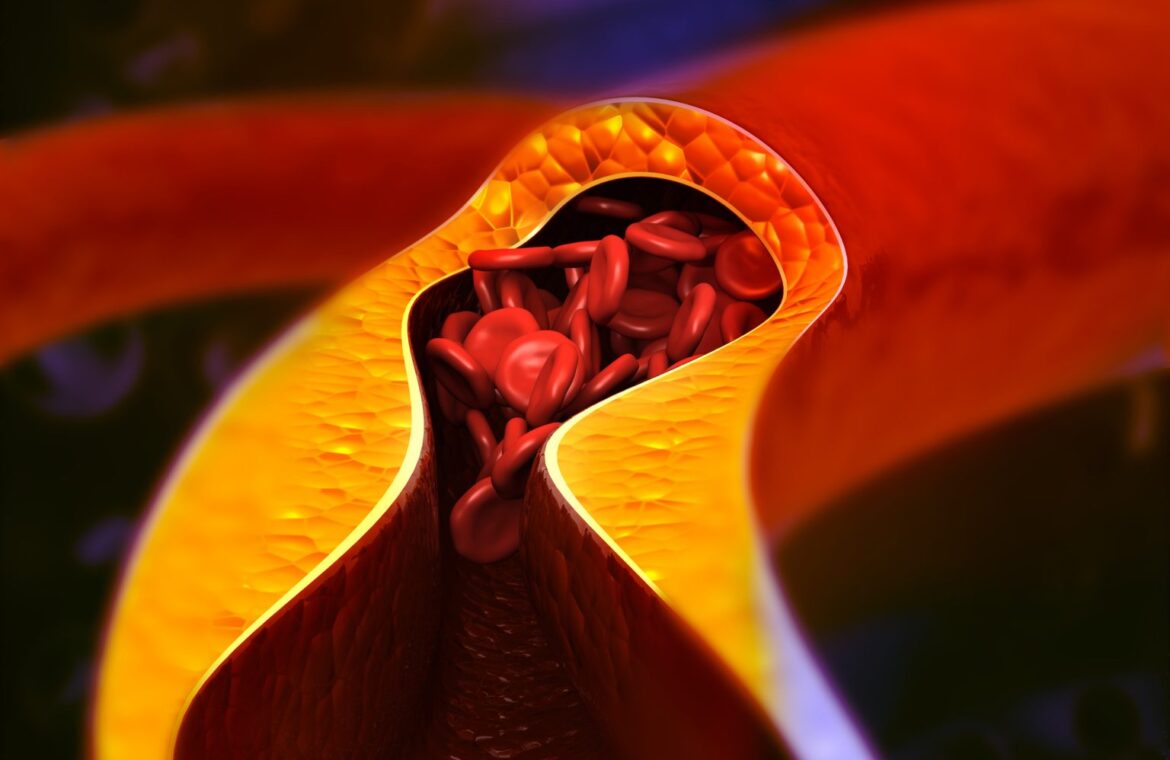

Οι φραγμένες αρτηρίες συχνά αναπτύσσονται αθόρυβα για χρόνια, ωστόσο ευθύνονται για τα περισσότερα εμφράγματα και εγκεφαλικά παγκοσμίως. Καρδιολόγοι προειδοποιούν ότι η αθηροσκλήρωση είναι ένας «σιωπηλός δολοφόνος» γιατί συνήθως δεν εμφανίζει συμπτώματα μέχρι να στενέψουν ή να αποφραχθούν πλήρως οι αρτηρίες.

Μία βασική υποκείμενη αιτία είναι η αθηροσκλήρωση – μία προοδευτική πάθηση κατά την οποία η πλάκα συσσωρεύεται σταδιακά στο εσωτερικό των αρτηριών, προκαλώντας στένωση και σκλήρυνση, συχνά χωρίς συμπτώματα για χρόνια. Ο καρδιολόγος Dr Saurabh Juneja, εξηγεί σύμφωνα με το Hindustan Times ότι αυτός ο «σιωπηλός δολοφόνος» μπορεί να αναπτυχθεί χωρίς εμφανή σημάδια μέχρι να προκληθεί σοβαρή βλάβη, οδηγώντας τελικά σε έμφραγμα ή εγκεφαλικό.